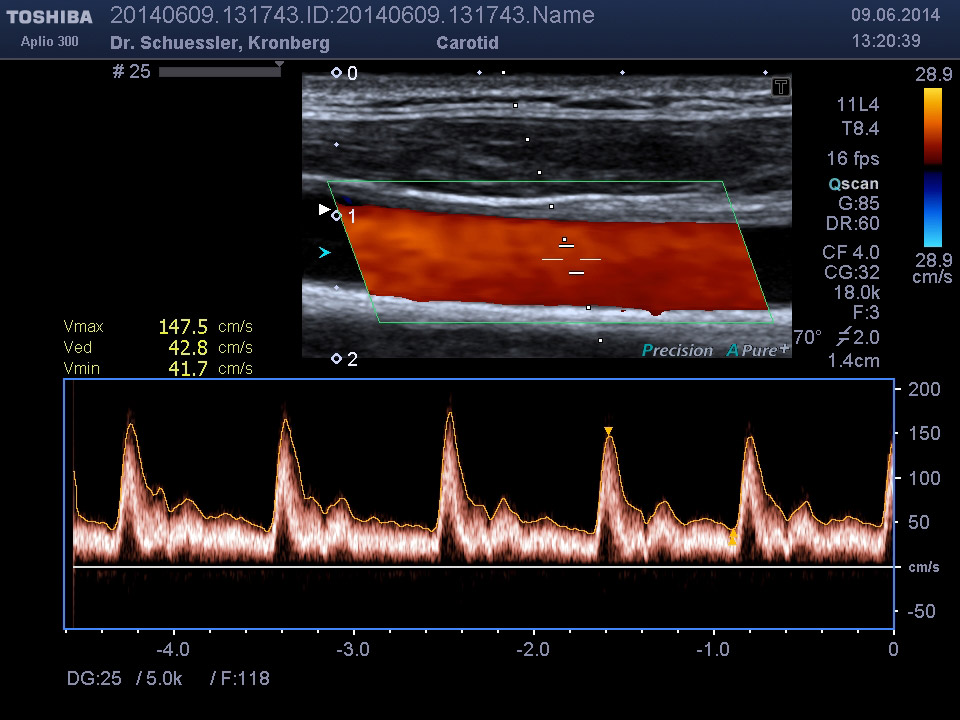

Die farbkodierte Duplexuntersuchung der Gefäße ist ein Ultraschallverfahren und gibt u.a. Auskunft über Verkalkungen, Einengungen, Verschlüsse oder Thrombosen im Bereich der Arterien und Venen.

Sie kann in allen Gefäßregionen des Körpers zur Anwendung kommen.

Die Untersuchung wird angewandt zur Diagnostik von Verengungen in den hirnversorgenden Arterien, Erweiterungen (Aneurysmen) oder Verengungen der Bauchschlagader, Verengungen der Nierenarterien bei Bluthochdruck,  Venenthrombosen und zur Bestimmung des Gefäßrisikoprofils.